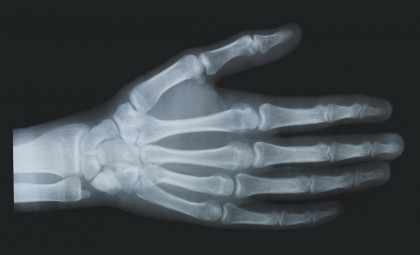

Rezultatele studiului arată că această combinație, cunoscută sub numele de D+Q, a avut efecte benefice asupra formării osoase, dar nu a redus resorbția osoasă. Mai mult, beneficiile D+Q au fost observate în principal la persoanele cu un număr mare de celule senescente, care au înregistrat creșteri semnificative în formarea osoasă și densitatea minerală osoasă la încheietura mâinii.